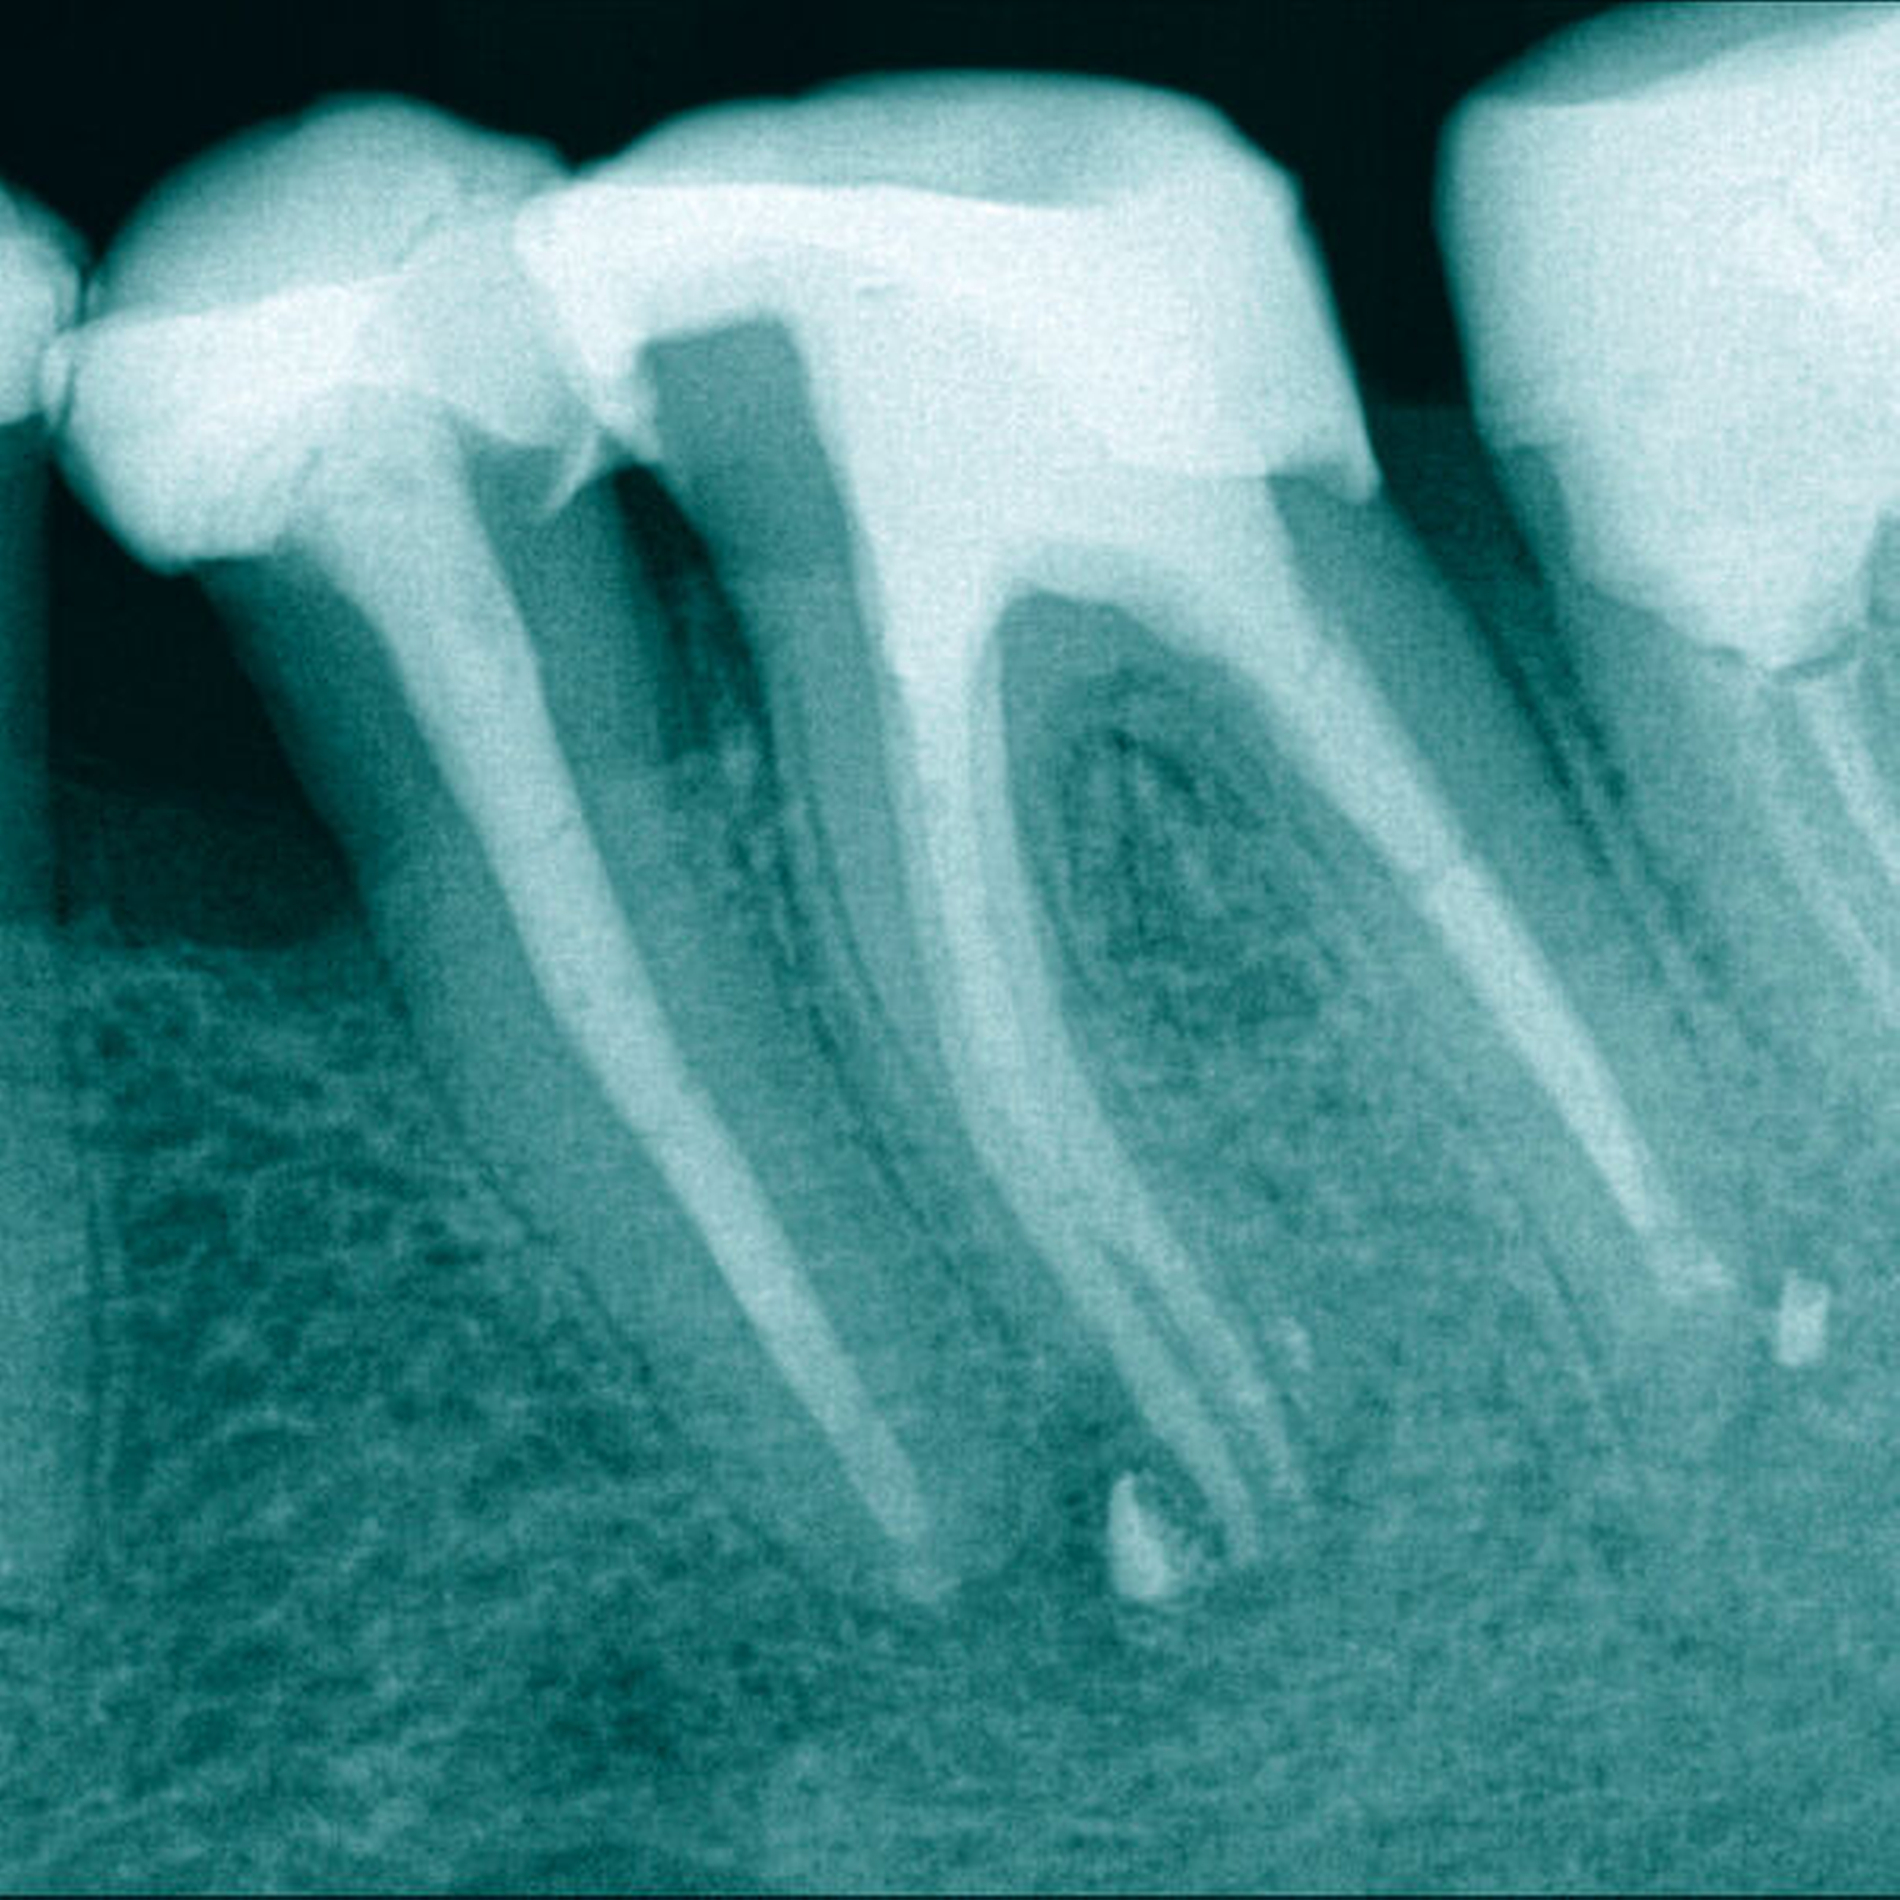

Ein 64-jähriger Patient wurde mit zwei frakturierten Hedströmfeilen in der distalen Wurzel von Zahn 46 überwiesen. Der Vorbehandler hatte versucht, das erste Fragment mit einer weiteren Hedströmfeile schraubend zu entfernen, jedoch frakturierte auch diese unter der hohen Torsionsbelastung (Abbildung 3).

Das eingeschraubte Fragment wurde koronal mittels Ultraschalltechnik (VDW Ultra, VDW, München, Deutschland; Endo-Chuck, B&L Biotech, Fairfax, USA) 3 mm freigelegt und aufgerichtet. Anschließend konnte das Fragment mit der Tube-Dorn-Apparatur gegriffen und entfernt werden (Abbildung 4). Daraufhin wurde Durchgängigkeit in allen drei Wurzelkanälen erreicht und es erfolgte die chemomechanische Aufbereitung. In der nächsten Sitzung wurde die Obturation mit Guttapercha und AH Plus (Dentsply Sirona, York, USA) warm-vertikal modifiziert nach Schilder durchgeführt (Abbildung 5).